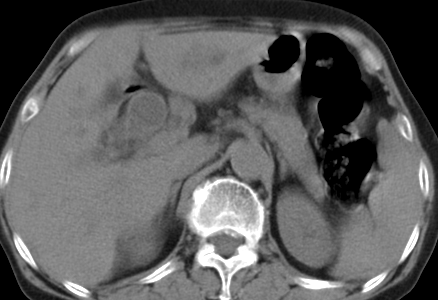

以下是引用齐原在2006-11-8 23:21:00的发言:[br]肝脏体积增大.肝表凸凹不平,肝内胆管扩张,胆总管扩张,胆总管末端突然截断,胰腺勾突增大,形态不规则.胰管扩张.考虑胰头癌.并低位梗阻性胆系扩张,胆囊炎.脾大.建议增强

以下是引用dyqct在2006-11-9 9:14:00的发言:[br]肝大,表面呈波浪状,肝内外胆管扩张,胆总管下端腔内见小结节状等密度影,胰管轻度扩张。胆囊显示不清。[br]考虑:1、胆总管下端占位性病变(等密度结石?壶腹部肿瘤?);[br] 2、肝硬化?[br] 3、建议增强扫描进一步检查。